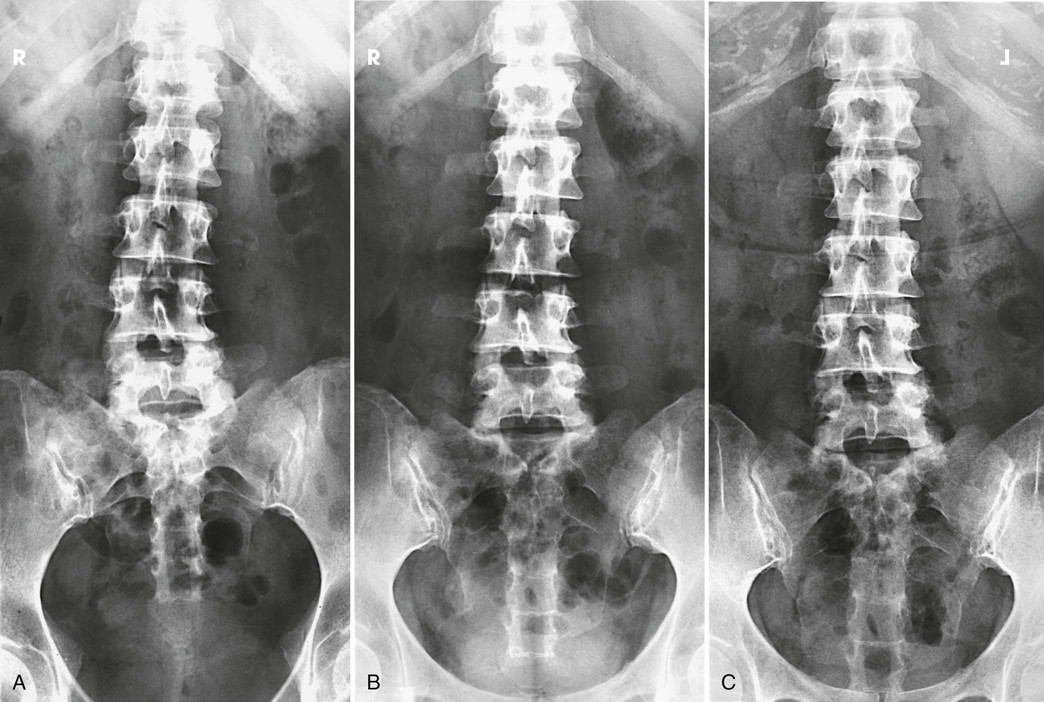

An AP or PA projection may be used, but the AP projection is more commonly employed. The AP projection is generally used for recumbent examinations. The extended limb position accentuates the lordotic curve, resulting in distortion of the bodies and poor delineation of the intervertebral disk spaces (Figs. 8-83 and 8-84). This curve can be reduced by flexing the patient's hips and knees enough to place the back in firm contact with the radiographic table (Figs. 8-85 and 8-86).

The PA projection places the intervertebral disk spaces at an angle closely paralleling the divergence of the beam of radiation (Fig. 8-87; see Fig. 8-84, C). This projection also reduces the dose to the patient.1 For this reason, the PA projection is sometimes used for upright studies of the lumbar and lumbosacral spine.

Structures shown, AP and PA

The image shows the lumbar bodies, intervertebral disk spaces, interpediculate spaces, laminae, and spinous and transverse processes (Fig. 8-88). The images may include one or two of the lower thoracic vertebrae, the sacrum coccyx, and the pelvic bones. Because of the angle at which the last lumbar segment joins the sacrum, this lumbosacral disk space is not shown well in the AP projection. The positions used for this purpose are described in the next several sections.

A radiologist may request or prefer that the AP projection be performed with the collimator open to the IR size. This projection provides additional information about the abdomen, in particular when the projection is done for trauma purposes. The larger field enables visualization of the liver, kidney, spleen, and psoas muscle margins along with air or gas patterns (see Fig. 8-88, B). CT and magnetic resonance imaging (MRI) are used often specifically to identify pathology (Fig. 8-89).